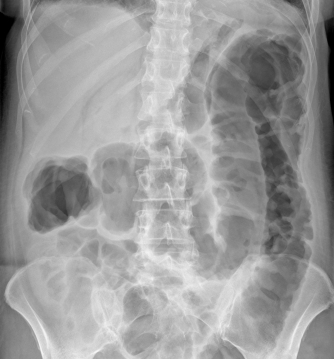

ДИАГНОСТИКА

Для постановки диагноза врач расспрашивает больного о его жалобах, исследует клинику заболевания, осматривает больного (пальпирует живот) и назначает лабораторное и инструментальное обследование: ирригоскопия, колоноскопия с биопсией, ректороманоскопия, УЗИ органов брюшной полости, ангиография сосудов брыжейки, исследование кала на копрологию, на яйца гельминтов, на кишечную группу, клинический анализ крови, биохимический анализ крови.